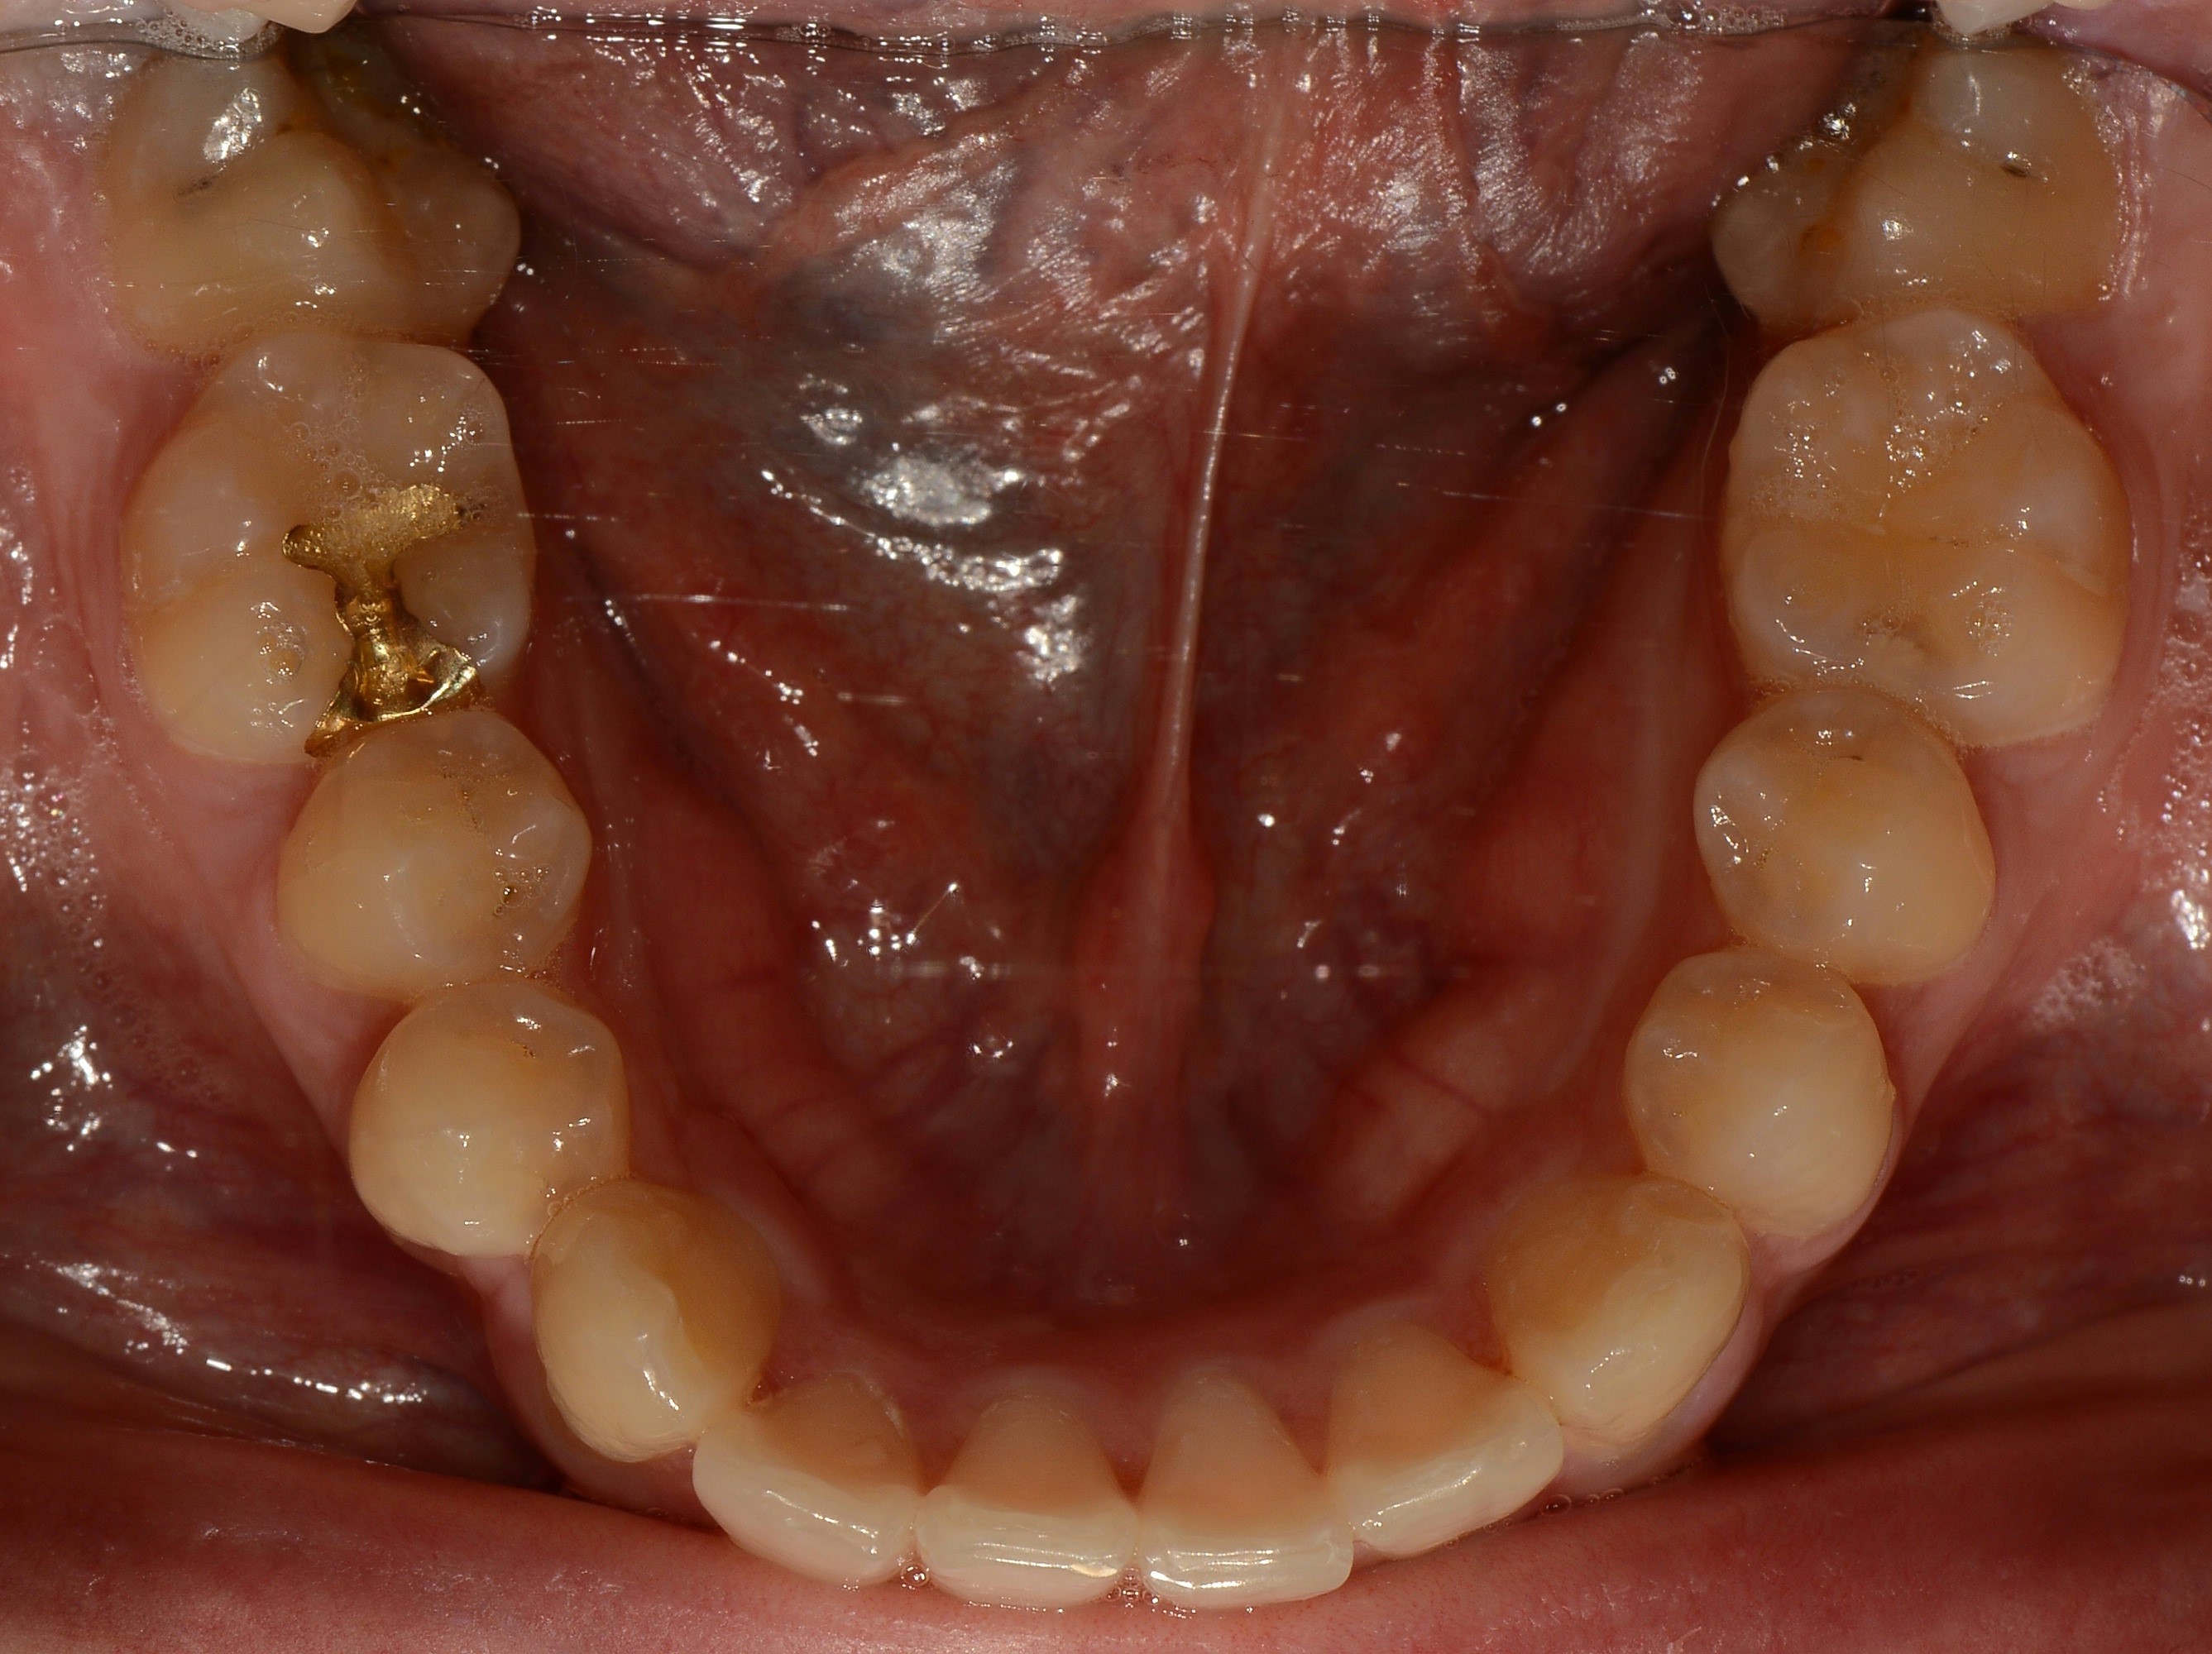

치료 전 사진입니다.